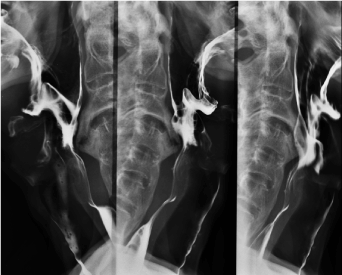

Due to the appearance of dysphonia and aggravation of dysphagia, he was admitted. Patient presented malnourished and dehydrated, with muscle flaccidity, cervical and axial skeletal rigidity. Another UDE was performed (Figure 3), which showed a bulge in the hypopharynx due to external compression – dysphagia lusoria. Computed Tomography (CT) (Figures 4 and 5) presented degenerative alterations affecting the cervical vertebrae with osteophytosys, reduction of discal spaces, subchondral cysts and anterior bridges syndesmotic. At the C3-C4 level, there was a large anterior osteophyte, which compressed the upper esophagus at the level of the vestibular fold (Figures 6,7 and 8). Due to malnutrition and repetitive aspiration pneumonias, feeding was started through a nasoenteral tube. Patient was referred for orthopedic surgeon to perform definitive treatment with resection of the cervical osteophyte.

Figure 6.  Computed Tomography: anterior cervical osteophyte formation

Figure 7. Computed Tomography: anterior cervical osteophyte formation.

Figure 8. Computed Tomography: anterior cervical osteophyte formation.